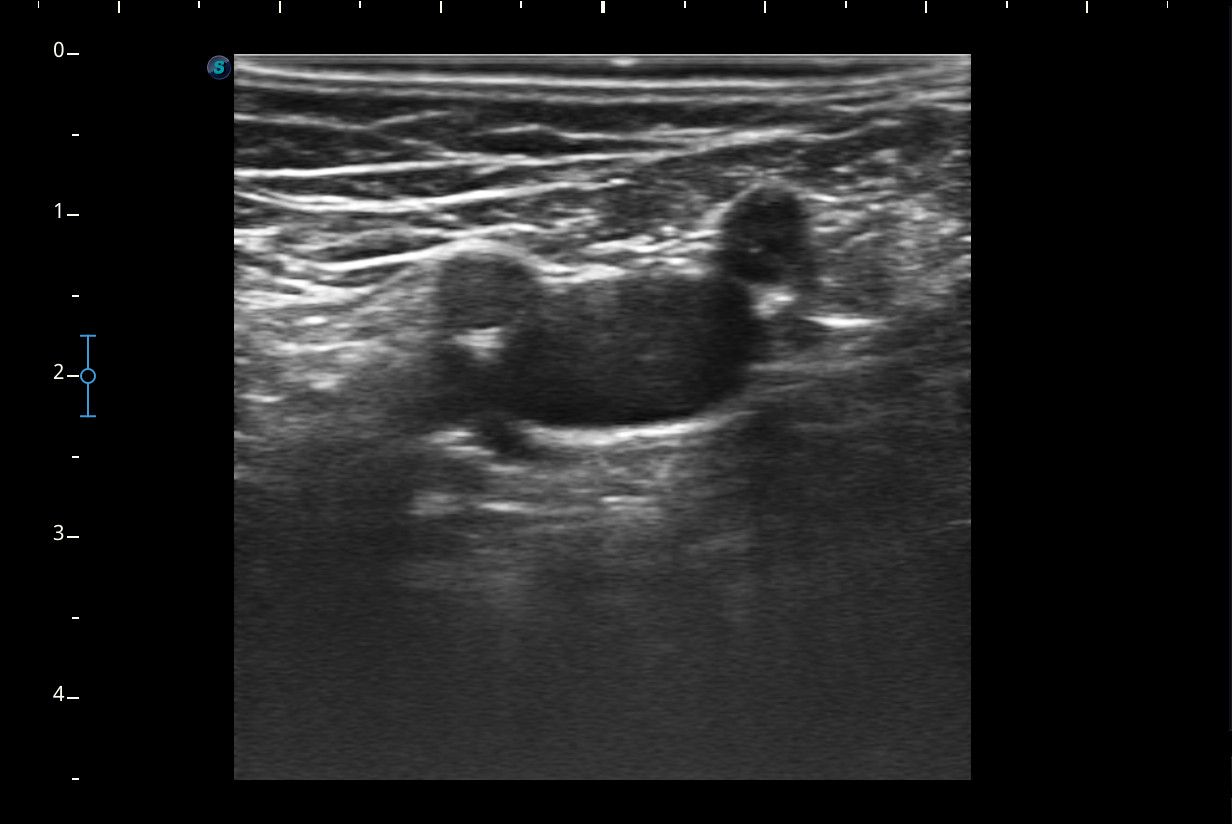

Mujer de 44 años, que presenta desde hace 2-3 semanas dolor e impotencia funcional en la pierna derecha con aumento de volumen y eritema de pantorrilla ipsilateral que en un inicio se trató como rotura fibrilar para la que se pauta reposo y tratamiento analgésico oral. Ha mejorado muy levemente pero persiste dolor en el hueco popliteo e impotencia funcional.Descripción de los hallazgos ecográficos y las imágenes más relevantes para la resolución del caso

A nivel del hueco poplíteo se visualiza presencia de trombosis de la vena poplítea, no así en localizaciones proximales.Otras pruebas complementarias realizadas (si existen)